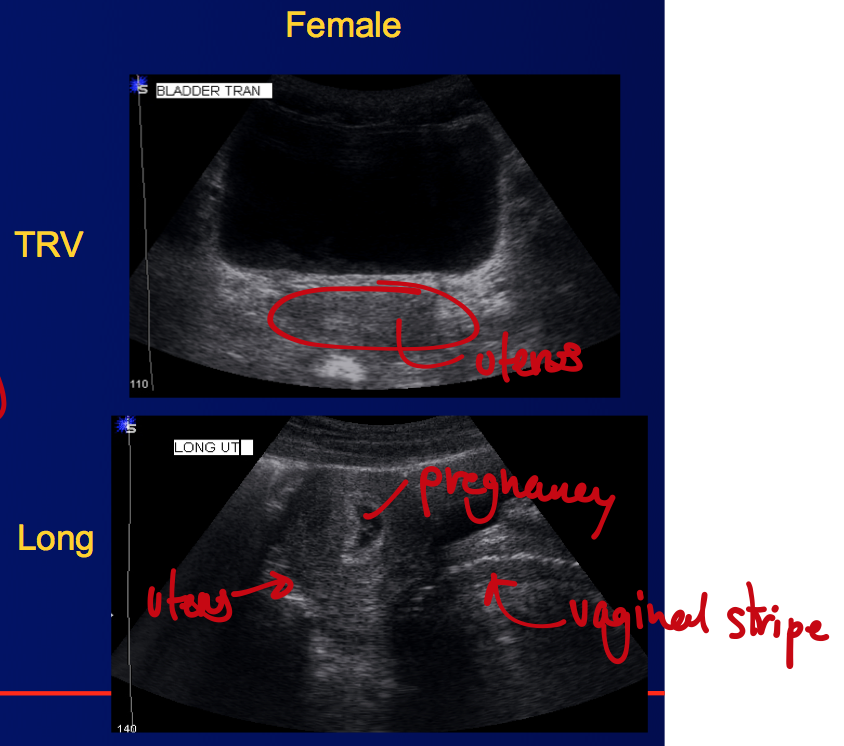

What’s this an image of?

Label the different structures (there are 4 of them between the 2 images)

This is the female pelvic region